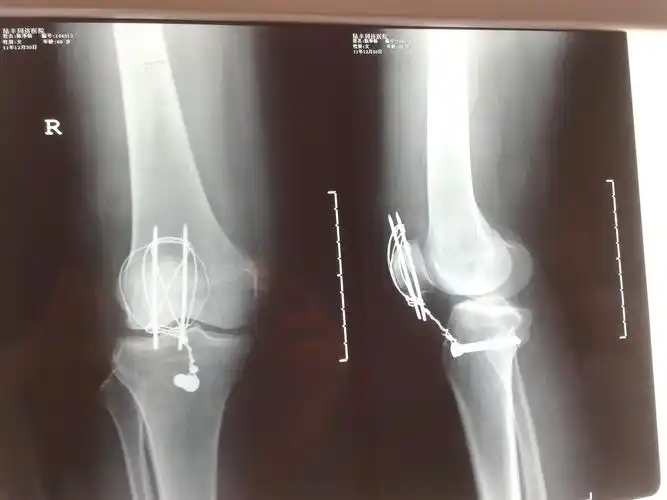

髌骨骨折术后两个月可以下地做饭吗?

这个髌骨骨折能否手术?

【病例讨论】严重髌骨粉碎骨折,有图求真相 [病例帖]

髌骨骨折.这样有错吗.